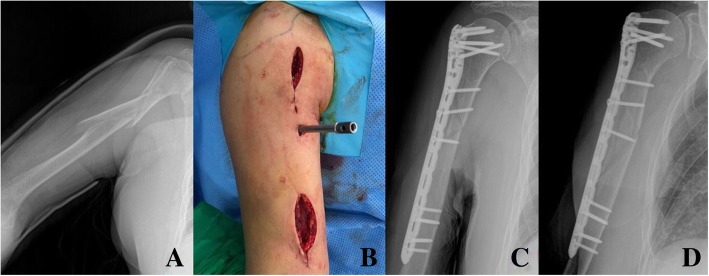

Fig. 5.

In a 85 year-old female patients after slip down injury, X-ray showed long spiral (Complex spiral type, AO classification: C1) humerus shaft fracture with proximal fracture extension to the greater tuberosity (a). In the midportion of the long philos plate, additional locking or compression screws were inserted through several small incisions for further rigid fixation (b). Long humeral philos plate could fix this complex humeral shaft fracture adequately (c, d)